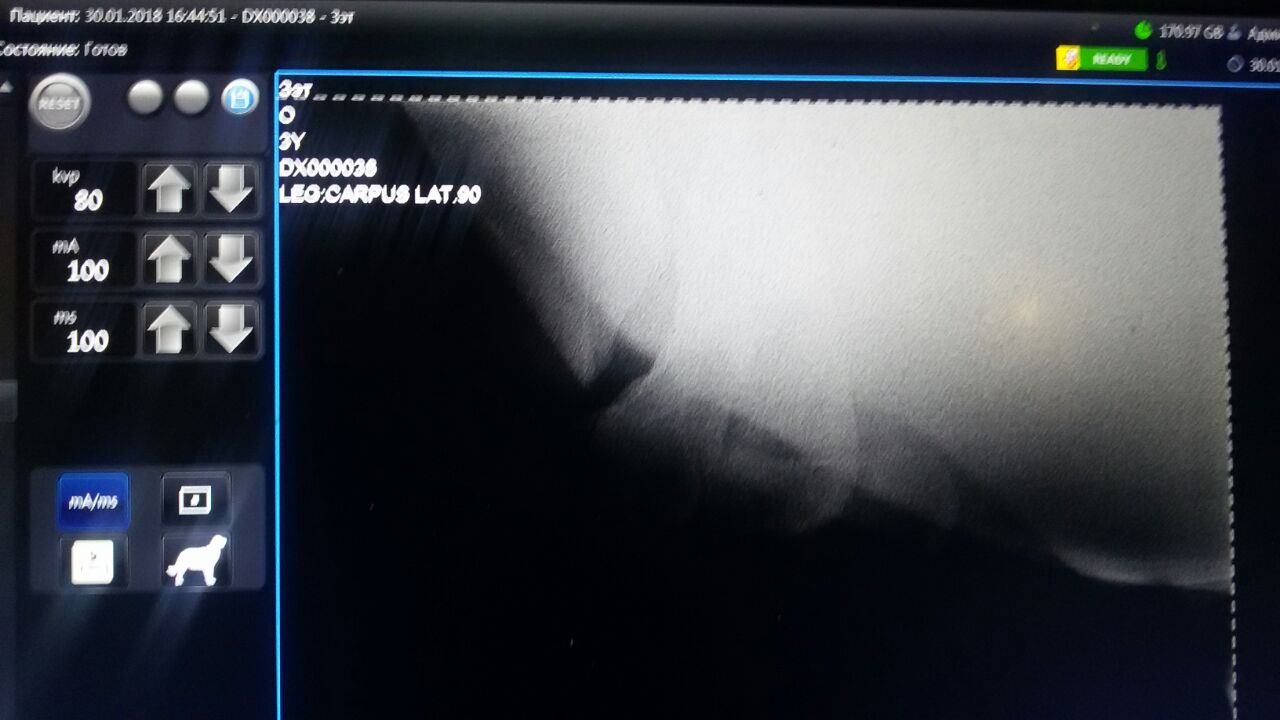

По приезду доктора, ближе к вечеру второго дня 30 января мы начали делать рентген.

Сложность заключалась в том, что отек ушел под локоть и на грудину. Снаружи отека не было. И отек мешал сделать рентген полноценно, но и достать поврежденную область не представлялось возможным!

Измучив коня для хоть какого- то нормального снимка, мы оставили его в покое и начали отсылать всем врачам, кого могли найти.

Один и тот же Диагноз поставили почти сразу несколько врачей " ПЕРЕЛОМ ПЛЕЧЕВОЙ КОСТИ СО СМЕЩЕНИЕМ"